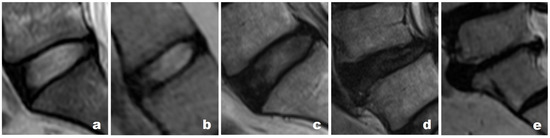

- Pfirrmann, C.W.; Metzdorf, A.; Zanetti, M.; Hodler, J.; Boos, N. Magnetic resonance classification of lumbar intervertebral disc degeneration. Spine 2001, 26, 1873–1878. [Google Scholar] [CrossRef]

- Griffith, J.F.; Wang, Y.X.; Antonio, G.E.; Choi, K.C.; Yu, A.; Ahuja, A.T.; Leung, P.C. Modified Pfirrmann grading system for lumbar intervertebral disc degeneration. Spine 2007, 32, E708–E712. [Google Scholar] [CrossRef]